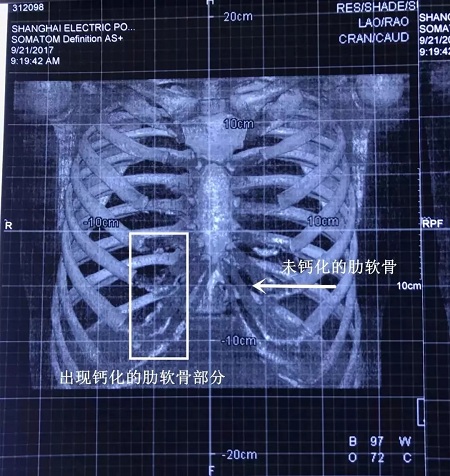

▼鈣化肋軟骨和未鈣化肋軟骨的影像區(qū)別

如上圖所示,鈣化了的肋軟骨和硬骨一樣,都是呈同樣密度的白色顯示,而正常的肋軟骨密度顯示是透明狀。

▼輕微鈣化的肋軟骨